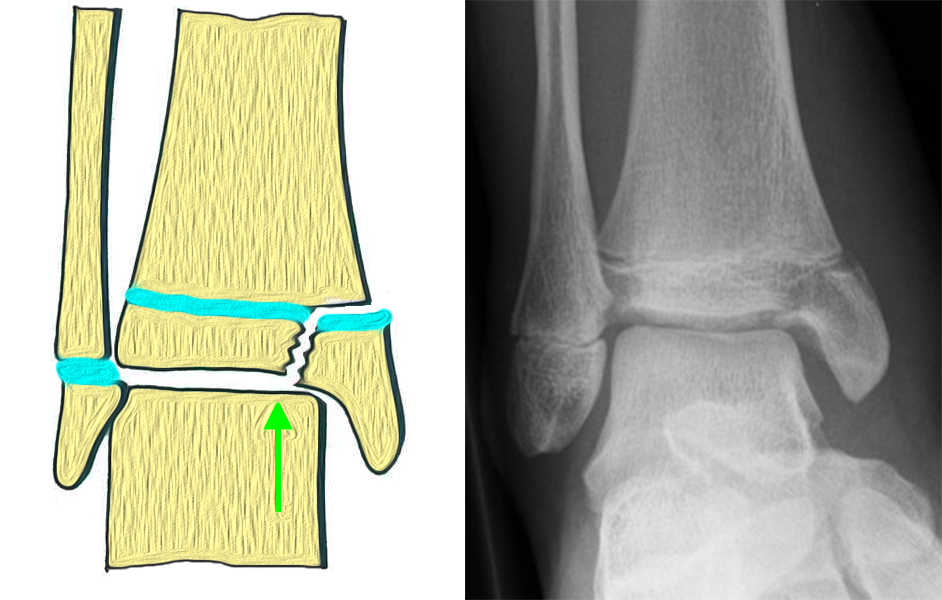

Bei den medialen Malleolarfrakturen handelt es sich um Fugengelenkfrakturen bzw. Aitken II und III Verletzungen. Kennzeichnend ist, dass der Frakturverlauf die wachstumsaktive Zone zur Epiphyse hin durchkreuzt. Die Verletzung der wachstumsaktiven Zone macht diese Verletzungen besonders problematisch.

Fugengelenkfrakturen treten typischerweise vor dem 10. Lebensjahr auf, in einer Phase, in welcher die Wachstumsfugen noch weit offen sind. Dieser Frakturtyp betrifft fast ausschließlich den medialen Malleolus. Laterale Frakturen sind extrem selten, teilweise kommt es zu lateralen Bandverletzungen oder Fugenschaftfrakturen der distalen Fibula. Die Frakturlinie verläuft in einer Verlängerungslinie von der medialen Taluskante nach proximal. Häufig stellen sich Verletzungen des Innenknöchels im Röntgenbild schlechter dar, insbesondere wenn die Aufnahmen verdreht sind oder die Ebene der Fraktur bei geringer Dislokation verkippt zur Röntgenebene liegt. Besteht klinisch der geringste Hinweis auf eine Verletzung des Innenknöchels, muss aufgrund der Tragweite der Verletzung durch entsprechende Aufnahmen gegebenenfalls auch Schnittbildverfahren die Verletzung sicher diagnostiziert oder ausgeschlossen werden (Abb. 15).

„Kadiläsion“- Mediale Malleolarfraktur

Bei kindlichen Verletzungen des medialen Malleolus handelt es sich nach L. v. Laer um eine sogenannte Kadiläsion, d.h. eine Verletzung mit hohem Risiko eines schlechten Behandlungsergebnisses bei nicht korrekter Behandlung. Selbst bei optimaler Therapie ist das Risiko für spätere Wachstumsstörungen hoch, sodass diese Verletzungen nicht selten ein juristisches Nachspiel haben. Durch die Verletzung der wachstumsaktiven Zone kann es zu einem vorzeitigen Verschluss der Wachstumsfuge kommen, mit entsprechendem Fehlwachstum. Das Risiko eines vorzeitigen Verschlusses der Wachstumsfuge korreliert mit dem Ausmaß der Schädigung der wachstumsaktiven Zone. Ab dem 13. Lebensjahr wird das Risiko bei reduzierter Wachstumsaktivität zunehmend geringer.

Fugengelenkfrakturen können die Wachstumsfuge durchkreuzen (Abbildung 16a), ohne oder nur mit minimaler Beteiligung der Fuge sehr weit medial liegen (Abbildung 16b) oder durch die Fuge auslaufen (Abbildung 16c). Relevant für die Wachstumsprognose ist weniger die Form der Fraktur, sondern das Alter des Patienten zum Zeitpunkt des Traumas sowie das Ausmaß der Schädigung der Wachstumsfuge, wobei eine Korrelation mit dem Ausmaß der Dislokation besteht.